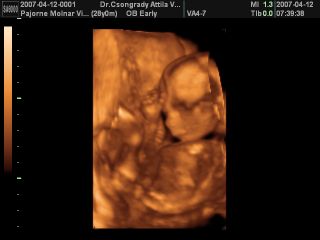

A fiamból 1000%-os LÁNY lett!

Mondta a doki, h biztos benne, h lány és megmutatta. :lol: :lol: :lol: Beterpesztett a lelkem, láttam a nuniját. :oops: Mutatta, h ott a kisajak, a nagyajkak. :wink:

De még nem merem magam beleélni, bár mondta a doki, h ritkán mondja biztosra, de most ez az.

Sztetek elhihetem, mert igazából szombaton a nő csak tippelt, mert oldalról látta, ott volt a lába és annyit mondott, h van ott valami, tehát vszinű fiú. :oops: Most meg szemből láttuk ahogy beterpeszett. :D